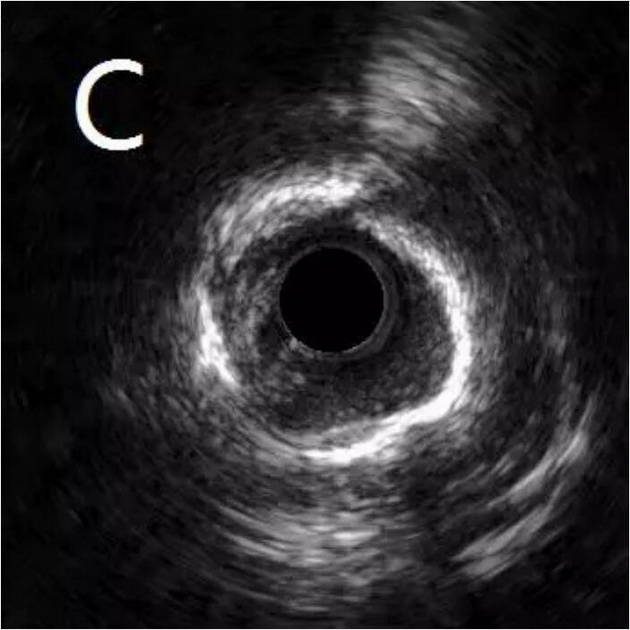

患者为77岁女性,因冠心病进行冠状动脉介入治疗,造影发现冠状动脉前降支不仅闭塞(图A),而且伴有钙化。通过不懈的努力,将闭塞的血管打开,但钙化处球囊无法将病变充分扩张(图B),意味着无法通过植入支架来维持血管管腔。于是采用血管内超声对病变处进行检测,显示病变处存在严重的360度环形钙化(图C、D)。